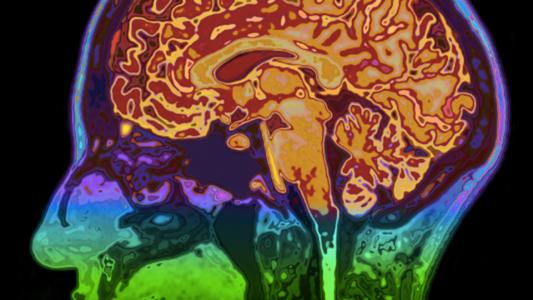

Could your brain regenerate like skin?

How to rebuild a broken brain

OpenBCI has developed technology that allows you to control the world outside your body with your brain waves.